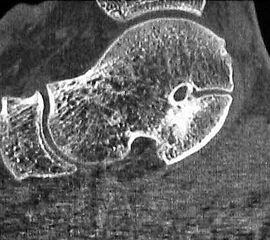

MRT und CT konkurrieren in der Fein-Darstellung der Knochenbrücke, der Beurteilung der nichtbetroffenen Anteile des Subtalargelenkes und der Sekundärveränderungen. Das MRT bietet den Vorzug, bindegewebige und knorpelige Strukturen (Abb. 2) und bei Einsatz von Kontrastmittel auch knöcherne Aktivierungsphänomene genau abzubilden; die knöcherne Feinstruktur und genaue Ausdehnung dagegen ist mit dem Dünnschicht-CT wesentlich exakter darstellbar (Abb.3). In manchen Fällen ist eine 3-D-Rekonstruktion des CT hilfreich. Besonders wichtig ist eine geeignete Schichtebenen-Wahl:

Diagnostisch sollte neben Röntgenübersichtsaufnahmen (indirekte radiologische Zeichen: Dorsaler Traktions-Osteophyt am Taluskopf, „talar beaking“; kontinuierliche Linie der Trochlea-tali-Kontur übergehend in die Sustentaculum-tali-Kontur, „C-Zeichen“ (Abb. 11) 10) immer die dreidimensionale Bildgebung eingesetzt werden. Das MRT (mit Kontrastmittel) kann die Struktur der Brückenbildung und z.B. die Qualität des Restgelenkes (Knorpel-Dicke) besonders gut abbilden; das Dünnschicht-CT zeigt die knöcherne Feinstruktur im Bereich der Coalitio und den oft sehr schrägen Spalt-Verlauf im Frontalschnitt dagegen häufig genauer. Meist findet sich die Überbrückung im Bereich der medialen Facette; die Schichten sollten jedoch bis weit nach dorsal beurteilt werden, da ansonsten dorsomediale Formen übersehen werden können. Rozansky et al 7 unterschieden fünf morphologische Typen auf der Basis von 3-D-CT-Rekonstruktionen. Allerdings ist eine prognostische Zuordnung bisher nicht möglich.